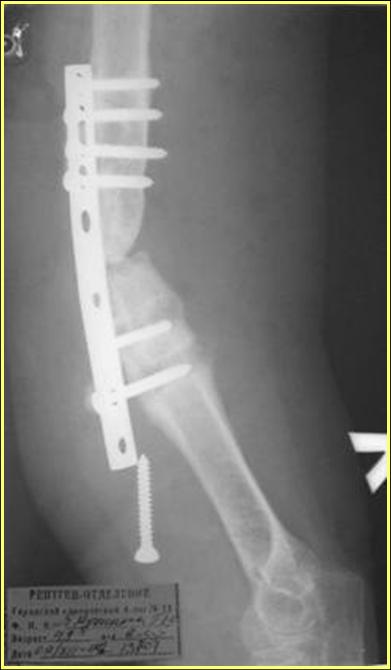

На примере два случая, извиняюсь за качество снимков, снимки и случаи из бывшего союза.

Первая больная с "успехом" была прооперирована 6 раз различными методами открытого и закрытого

остеосинтеза, включая то, что в Кисловодске заезжим австралийским "кудесником" на ложный сустав уложена скорлупа от страусиновых яиц. Последняя операция одиноким локинг плейт в одной из клиник.

Через год по поводу тех же проблем сделали ревизию, оригинальную пластину оставили как есть, только укрепили добавлением еще одной пластины и сделали костную пластику.

Через два месяца увидели признаки консолидации.

Второй случай, также после множественных операций:

пластина, аппарат, серкляж и парез нерва.

Также ревизия, из-за низкого состояния доступ был

сделан через остеотомию локтевого отростка.

Ложный сустав фиксирован двумя локинг плейт с

аутокостной пластикой, также через два месяца увидели признаки консолидации.

Движение в суставе разрешили в две недели.